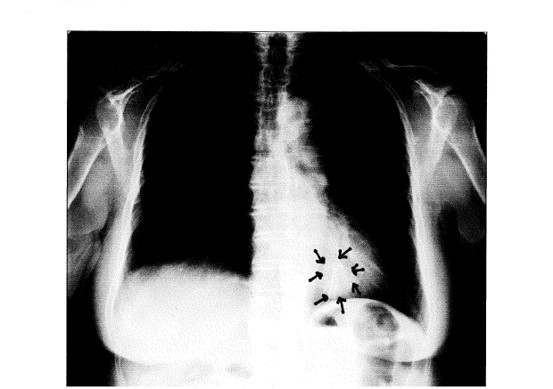

高級マンションの天上・床下の配線や、配電盤の電磁波をベットのコイルが増幅

ベッドのスプリングコイルは、床下にある電気配線から出る人口電磁波を増幅し、その上で寝る人を電磁波が原因の病気にさせている。スプリングコイルの入っているベッドはやめるべきだ。